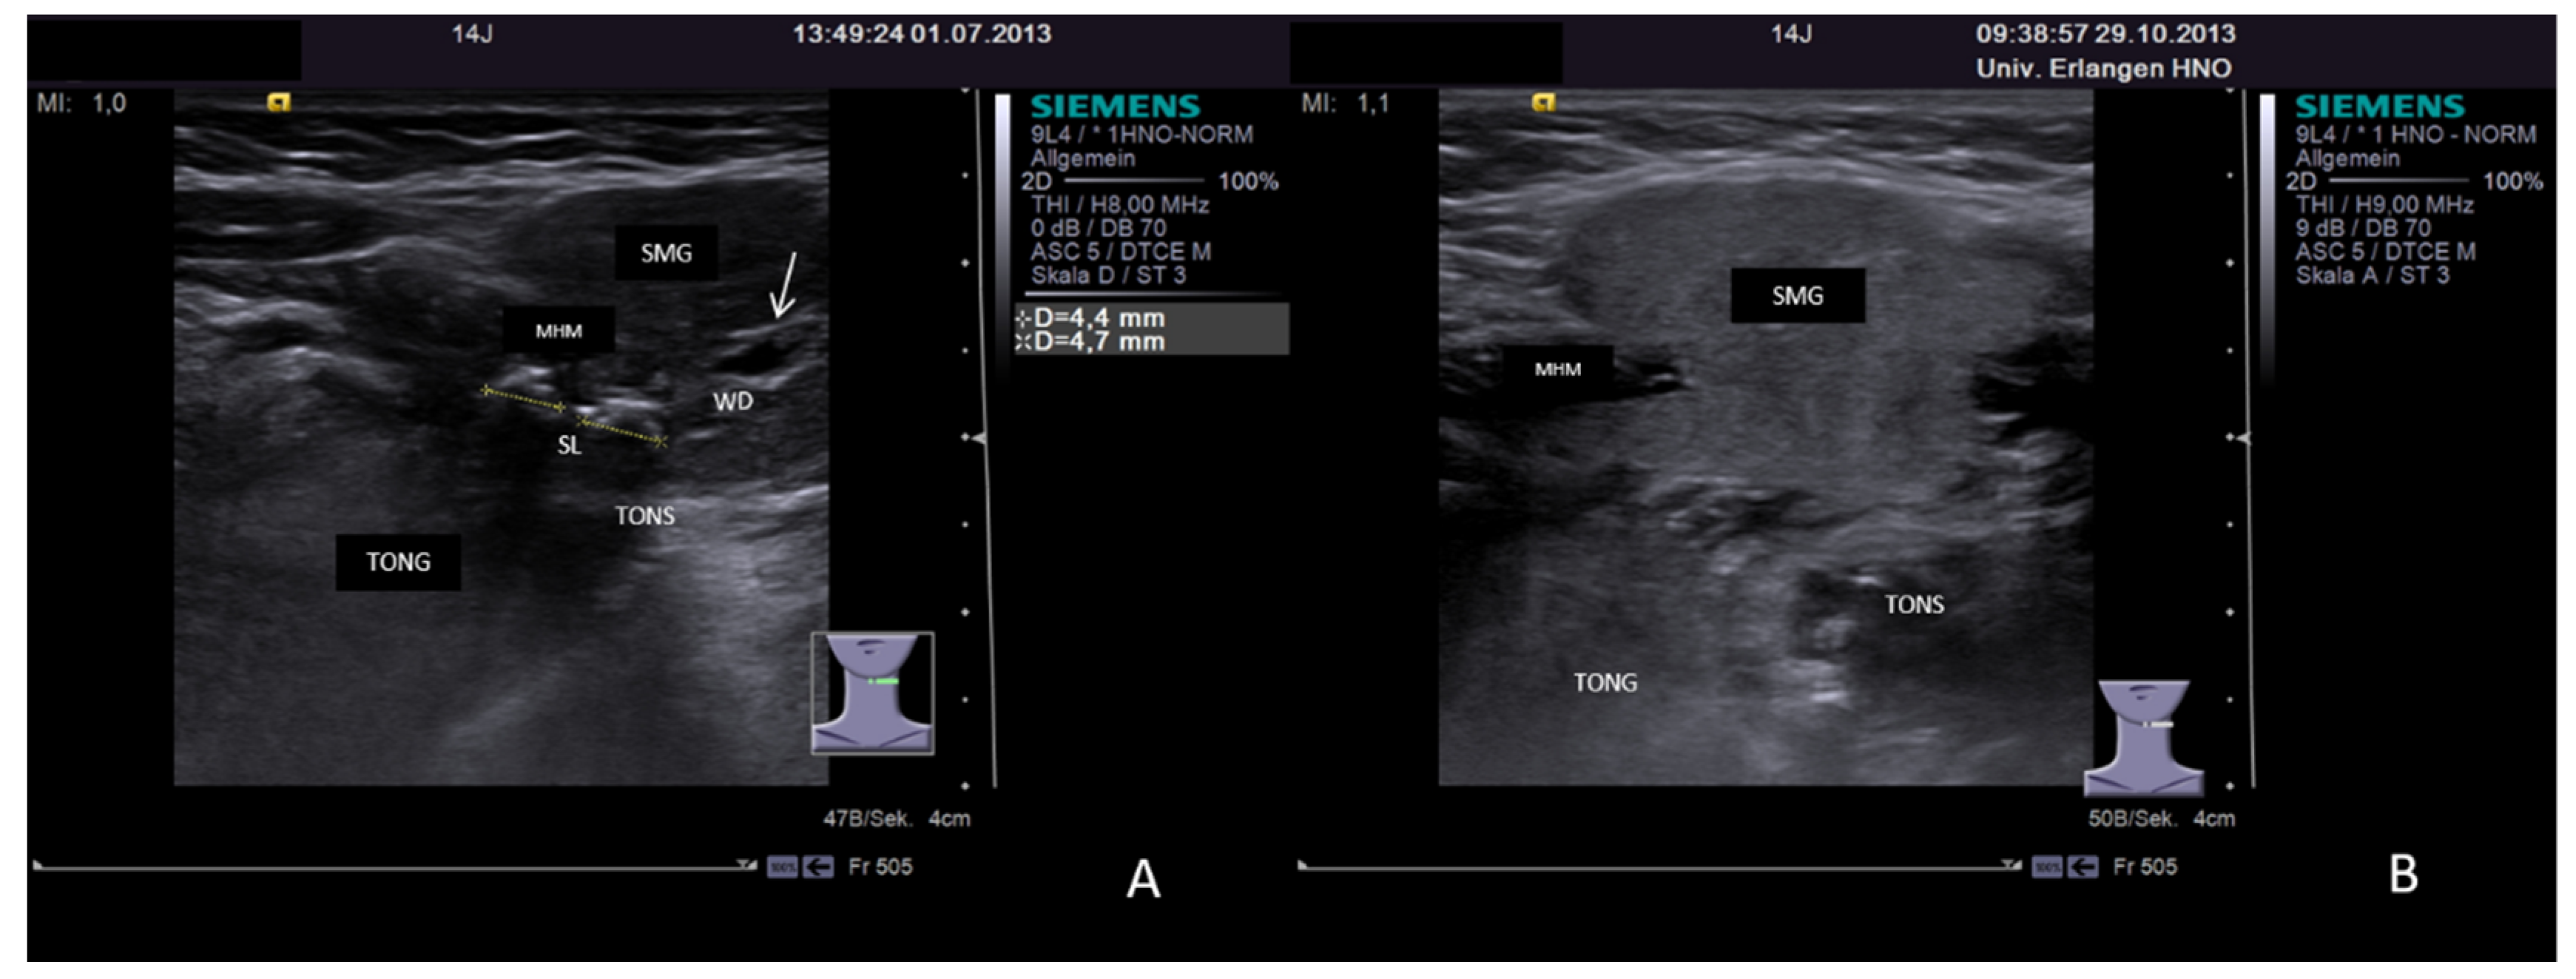

3.3.2. Obstructive Sialadenitis Caused by Sialolithiasis

3.3.3. Non-Sialolithiasis-Caused Unspecific Sialadenitis with Sialodochitis and/or Duct Stenosis with Primary or Secondary Obstruction